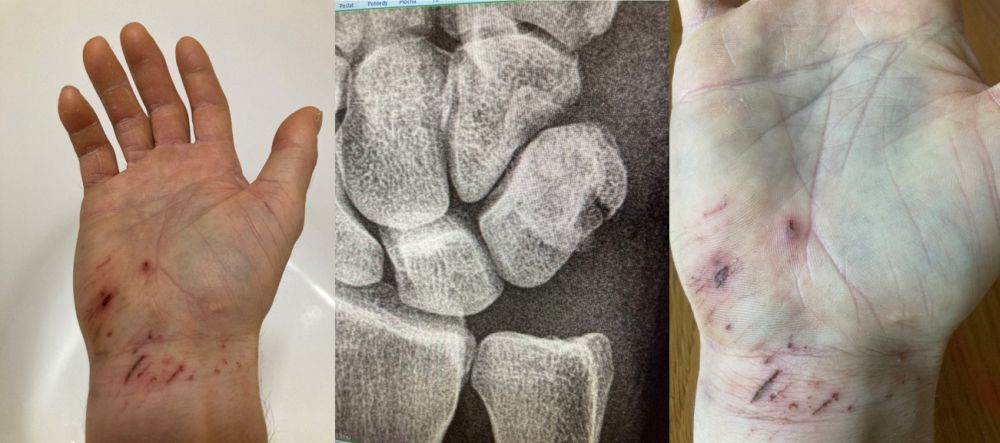

Jelikož se nevyrábí výrobek určený pro jištěné sólo, tak jakékoliv řešení bude vždy kompromisem. Buď bude mít méně hladké fungování, což snižuje pravděpodobnost přelezu, nebo se bude snižovat bezpečnost. Pro úplnost je potřeba zmínit výrobně dávno ukončený a nyní „investiční“ Silent Partner, který je dostupný už jen na Ebay. Tento je však pro limitní sportovní lezení stejně nevhodný. Dlouho jsem tedy přemýšlel nad analýzou rizik. Pak jsem se kvůli snaze o maximální eliminaci všech možných rizik paradoxně dostal do situace, kdy jsem po x úkonech ztratil fokus a při čištění cesty spadnul pár metrů na zem. Kromě pár pohmožděnin jsem si bohužel zlomil hráškovou kost na ruce. Naštěstí docela „dobře“ a bez sádry. Ale na nějakou dobu samozřejmě bez lezení.

Zpátky k lezení. Loni na podzim jsem kvůli expedici v Pákistánu a z ní přivezeném střevním dárečku, ale i kvůli práci a podobným „dospěláckým“ důvodům, neměl moc času cestu vylézt, resp. výkonnost na přelez byla, ale počasí už ne. Takže kalendář jsem otočil podruhé. Na začátku dubna jsem byl v dobré formě a LRS systém jsem měl konečně docela dobře vyladěný. Byla ale až moc velká zima na malé chyty. Dostal jsem se do high pointu, kde jsem při cvičném kontrolovaném odskoku měl vyzkoušené, že pád může být delší, ale ne nebezpečný. Nicméně ve dvouprstovce jsem vůbec necítil zmrzlé/odkrvené prsty a vypadnul jsem. Více od stěny než při testu. Letěl jsem do oblouku a přibilo mě to do stěny. Slanil jsem a s bolestí na připraveném druhém laně vyšplhal nahoru vyčistit materiál. Dobelhal jsem k autu, a ještě dojel domů. Zlomená pata na více kusů, ale alespoň tak, že se to obešlo bez šroubů, resp. operace. Nechodící sádra na měsíc, a další s francouzskými holemi. Vzpomněl jsem si samozřejmě na Dave McLeoda, který si také zranil kotník při dlouhém pádu v Rhapsody. Dlouhodobý projekt, který poté vylezl…